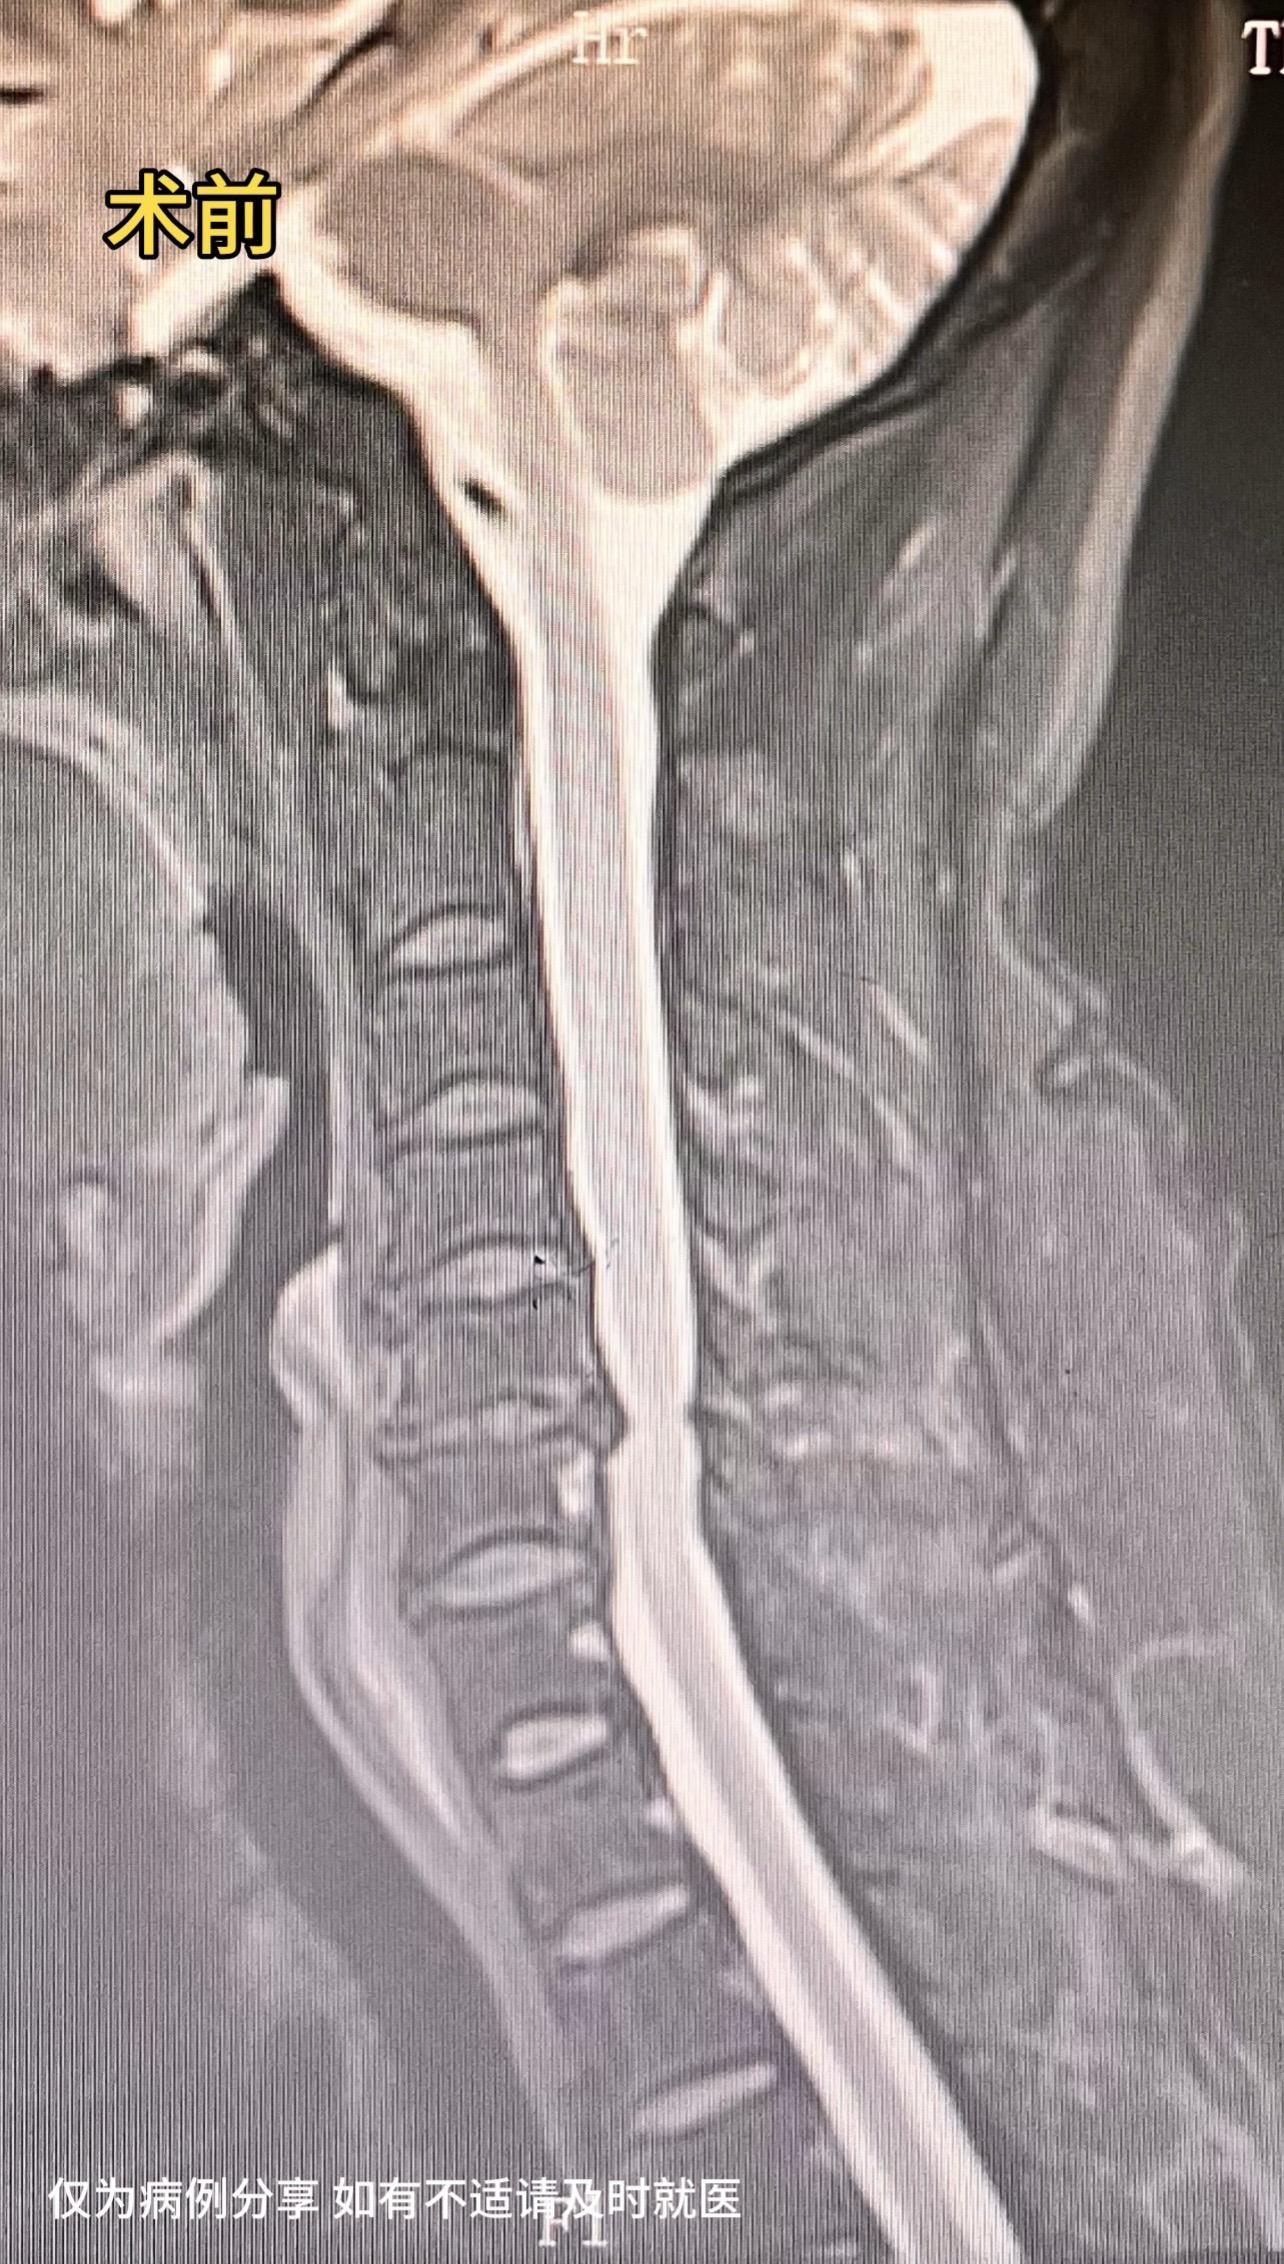

50岁女性,四肢麻木3年加重1年,双下肢重,偶有下肢踩棉花感。患者感觉很痛苦,看了好多医院,片子看着并不太重。2个月前在我科行保守治疗,效果差。后建议去北京协和会诊,协和说有手术指征,但不大。患者又返回我院,要求手术治疗,与患者沟通手术效果欠佳可能性大,但患者仍坚持手术治疗。术后患者双下肢麻木大大缓解,对手术效果十分满意。患者的理解信任是我们前进的动力源泉。